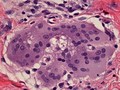

Multinucleated giant cell containing an asteroid, microscopy.

William R. Geddie